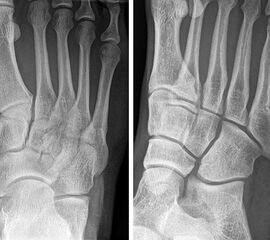

Abbildung 3

In der Literatur herrscht weitestgehend Einigkeit darüber, dass Lawrence und Botte Zone I Frakturen (Abb. 3) konservativ behandelt werden können 151617. Allerdings variieren die beschriebenen konservativen Behandlungskonzepte stark. Empfohlen werden die elastischen Wickelung bis zur Immobilisation im Unterschenkelgips/-walker, sowie die schmerzabhängige Vollbelastung bis zur vollständigen Entlastung 18. Häufig werden eine Dislokation von mehr als 2 mm, oder die intraartikuläre Fraktur (>30% der Cuboid-Metatarsalen Gelenkfläche) als Operationsindikation angesehen. Allerdings ist den Autoren keine prospektive Studie bekannt, welche ein konservatives gegen ein operatives Therapieregime verglichen hat. Egol et al. 15 publizierten eine prospektive Studie zur frühfunktionellen Nachbehandlung (schmerzabhängige Vollbelastung und festes Schuhwerk) von 49 Patienten mit einer Lawrence und Botte Zone I Fraktur (50% Intraartikulär, 32% > 2mm Dislokation). 94% der Patienten konnten nach 6 Wochen den Fuß voll belasten. Die mittlere Zeit der Arbeitsunfähigkeit betrug 22 Tage. Die volle Sportfähigkeit war bei 86% der Patienten nach 6 Monaten, bei allen Patienten nach einem Jahr erreicht. Weder der Grad der Dislokation noch die intraartikuläre Beteiligung hatten einen signifikanten Einfluss auf diese Zielparameter.